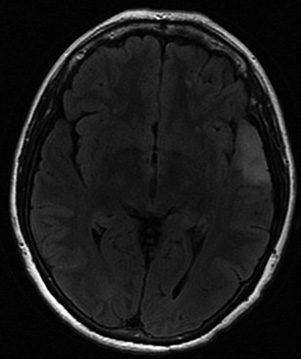

Femme âgée de 49 ans, crises épileptiques partielles complexes d’apparition récente.

Imagerie IRM conventionnelle :

Lésion temporo-insulaire gauche (gyrus temporal supérieur) cortico-sous-corticale.

Lésion assez bien limitée, en hypersignal FLAIR homogène et sans œdème périlésionnel. Effet de masse très discret.

La masse est en T1, avec une discrète prise de contraste mal limitée à prédominance corticale